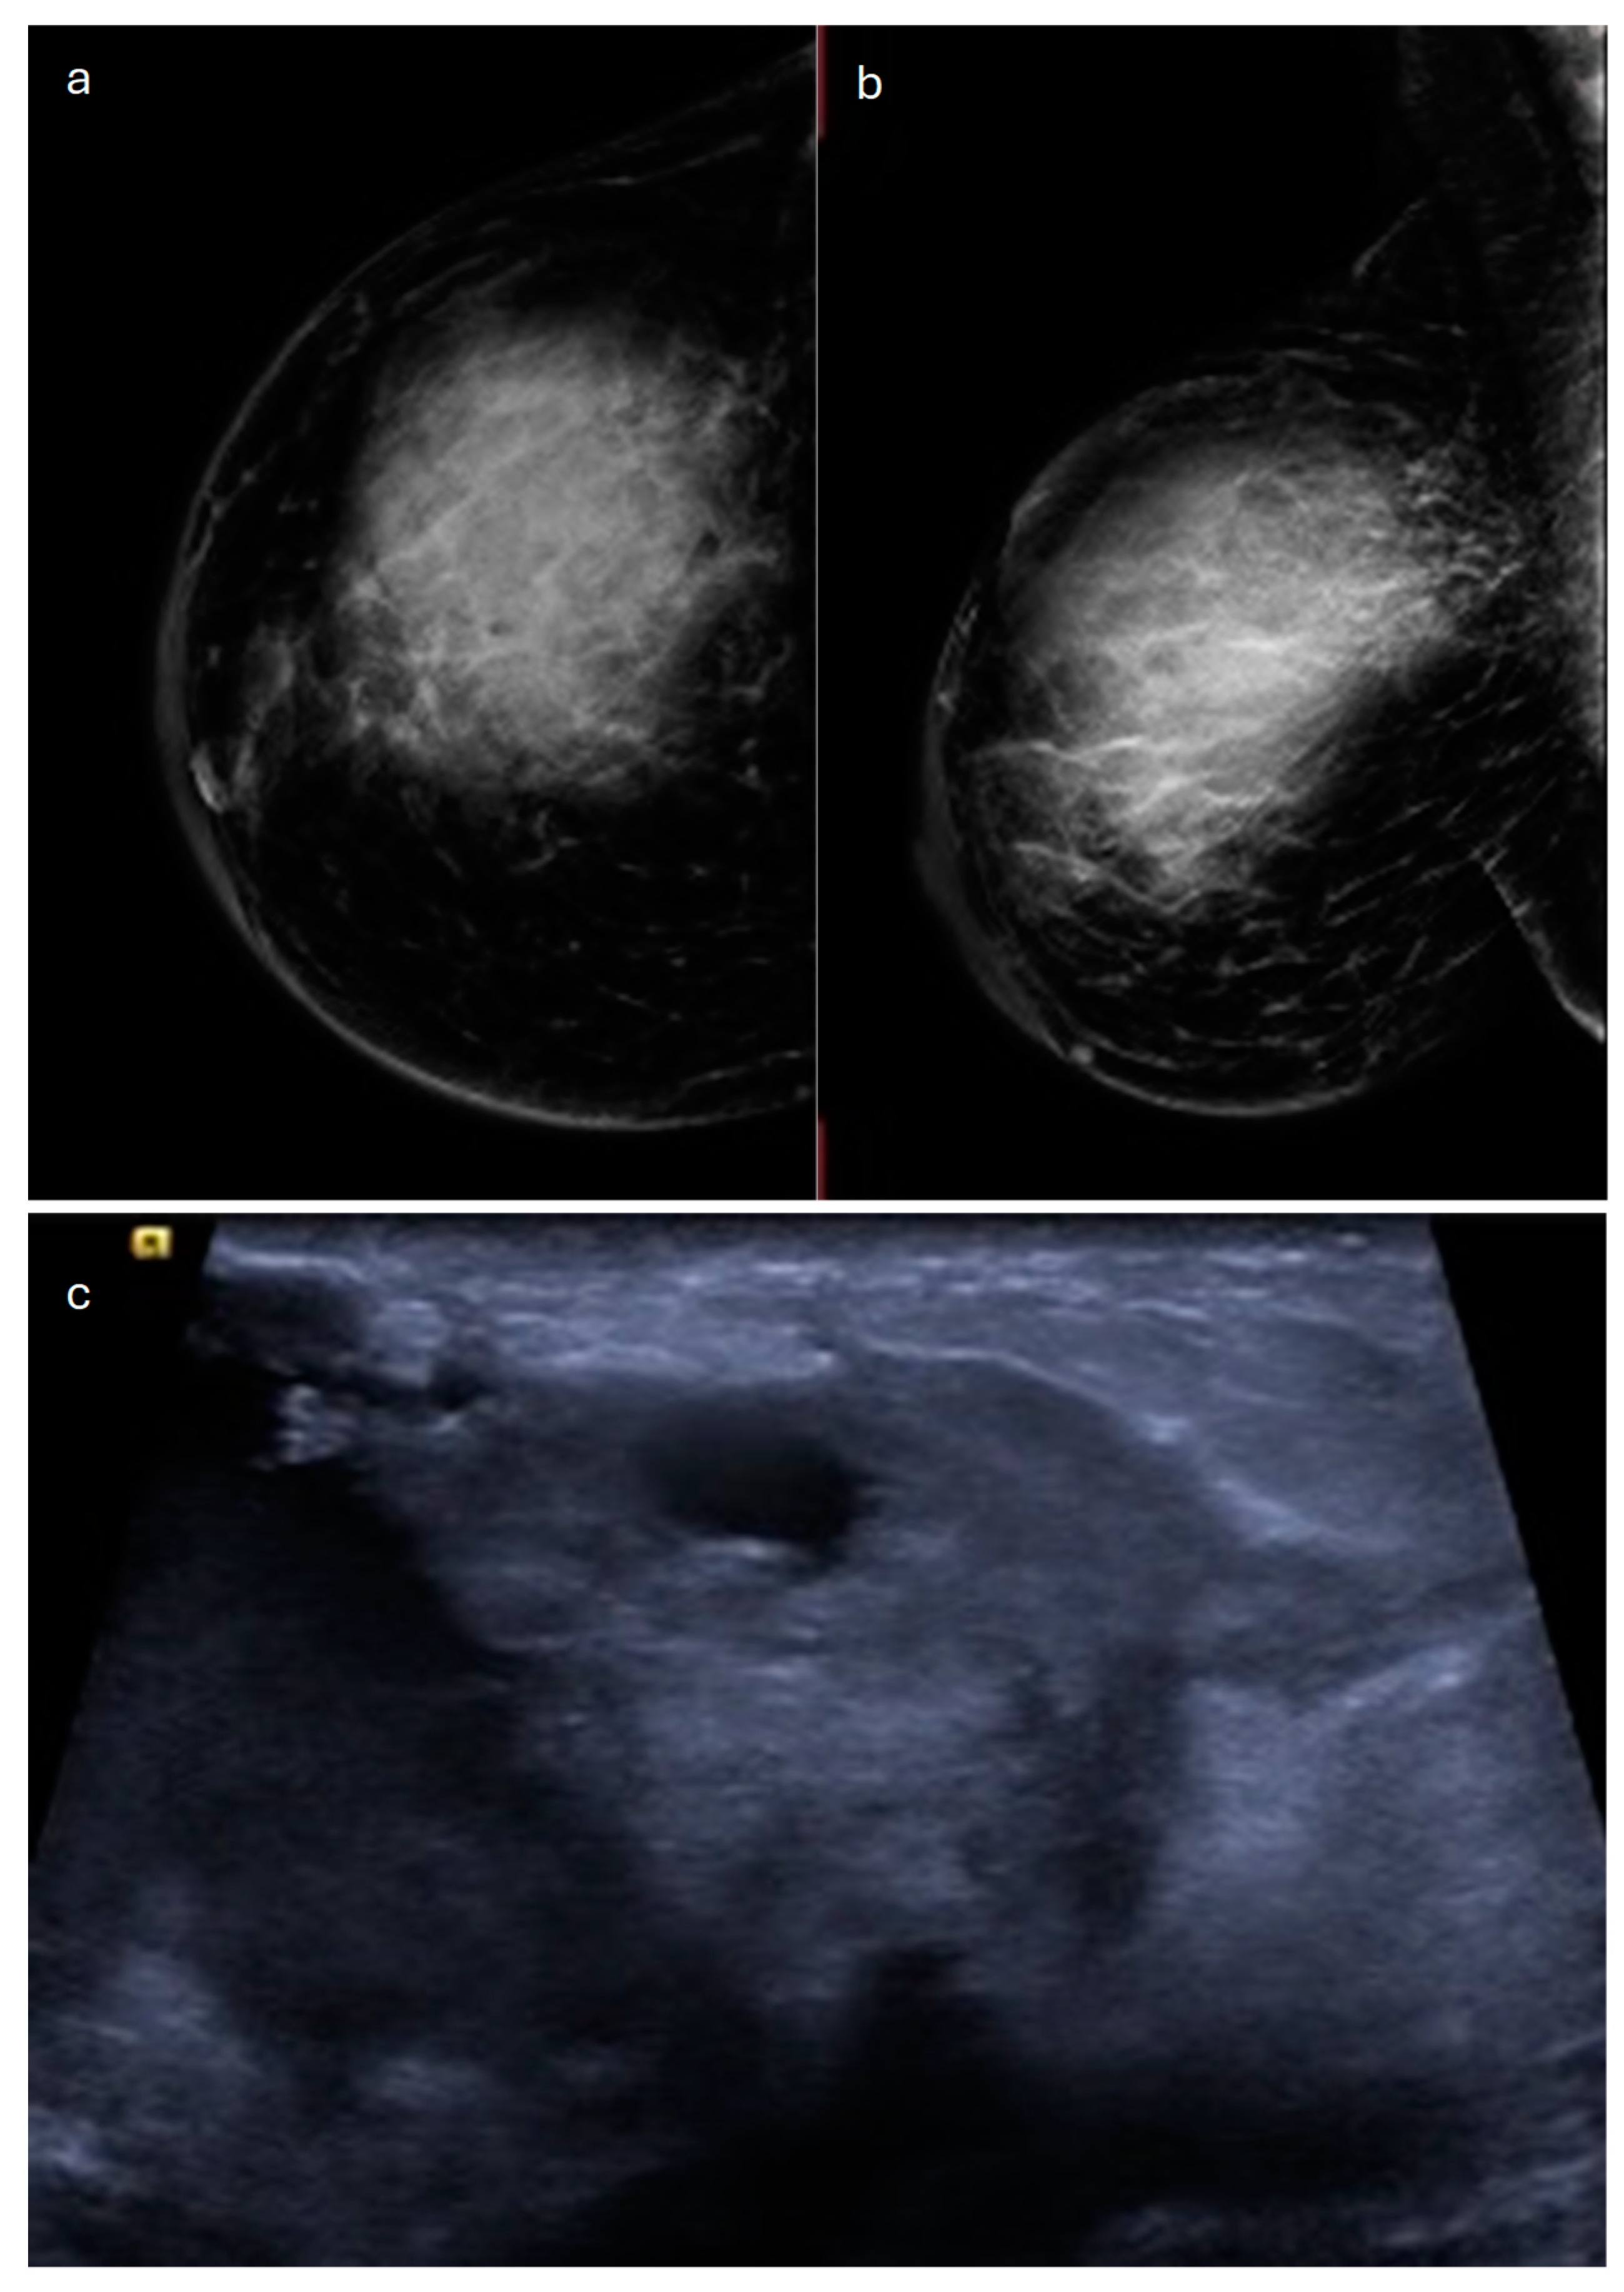

2. Lobular (Classic, Pleomorphic and Florid Types)